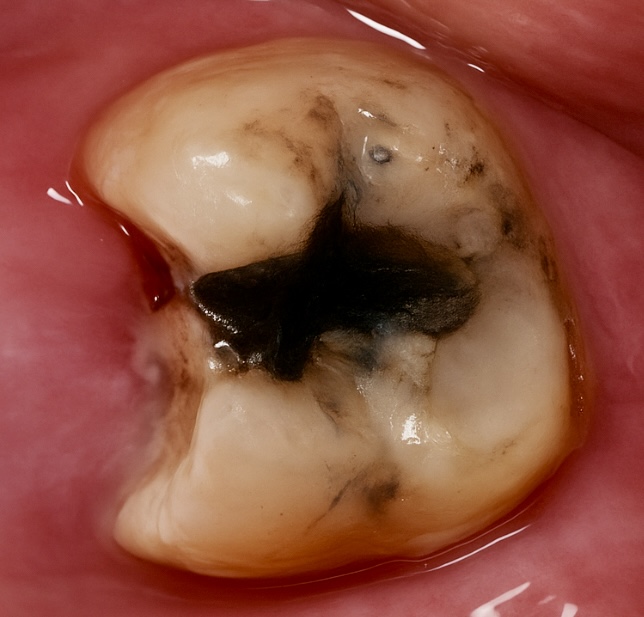

1. Initial Presentation

The patient presented with a deep occlusal-proximal carious lesion and discoloration (Fig 1). The tooth was sensitive to cold and percussion, confirming irreversible pulpitis on vitality testing. Radiographic assessment revealed pulpal involvement but sufficient ferrule for adhesive restoration.